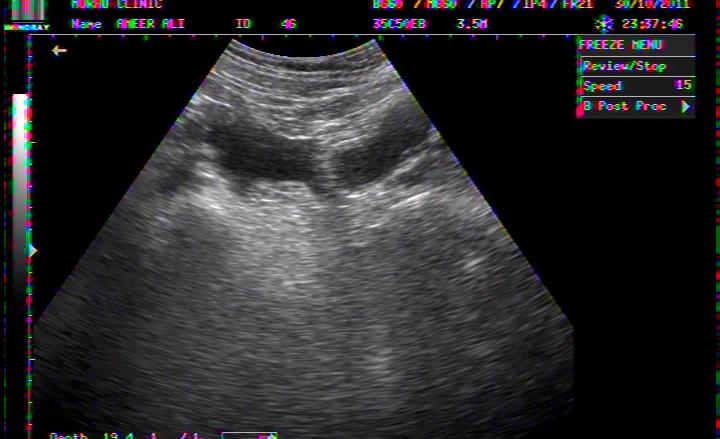

PERICHOLECYSTIC FLUID COLLECTION IN DHF